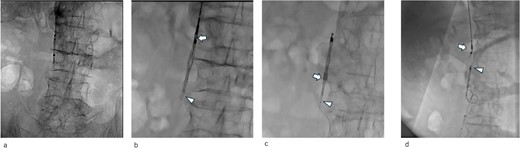

An IVCF was inserted into the inferior vena cava (IVC) using the right internal jugular venous approach. After performing IVC venography (Fig. 2a) using a driver sheath, the IVCF was attempted to deployed. However, the IVCF did not open (Fig. 2b). To retrieve the unopened filter, a plunger was pulled; however, the IVCF and plunger detached (Fig. 2c). We attempted to remove the IVCF via a right femoral venous approach using a snare. However, the snare did not pass through the IVCF because the tip of the leg was attached to the IVC wall or gonadal vein ostium. The hemodynamics of the patient worsened during the procedure. Therefore, we decided to quit additional endovascular retrieval and place a new IVCF. A new IVCF was placed to hold the unopened IVCF at the proximal (head) portion of the unopened IVCF through a right jugular approach (Fig. 2d). An unopened IVCF was placed with pulling the delivery sheath (Fig. 3).

Abdominal X-ray image after the surgery. Two inferior vena cava filters are placed.

Despite being effective in avoiding the migration of the unopened IVCF and treatment of the acute pulmonary thromboembolism, our approach remained of concern. IVCFs have been reported to cause chronic perforation to the IVC wall, even with appropriate deployment [9]. In this patient, the tip of the unopened IVCF was folded (Figs 3 and 4c); thus, the risk of perforation increased because of the stiffness of the folded IVCF legs. Therefore, close monitoring is required.